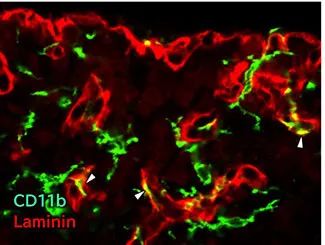

在中枢神经系中,层粘连蛋白几乎只在血管周边的基底膜中表达,被用作血管的标志物。既往的研究显示,脑血管基底膜内层(内皮侧)含有层粘连蛋白-411和-511,而外层(脑实质侧)含有层粘连蛋白-211和-1111),参与血脑屏障(BBB: Blood-Brain Barrier)的形成与功能。

“抗层粘连蛋白,豚鼠”是豚鼠来源的层粘连蛋白多克隆抗体,可用于免疫组织染色中的多重染色2-6)。

物种:小鼠

部位:海马体

样品:冰冻切片

抗体浓度:1:500

数据提供:京都工艺纤维大学 应用生物学系 宮田老师

物种:小鼠

部位:延髓最后区

样品:冰冻切片

抗体浓度:1:500

数据提供:京都工艺纤维大学 应用生物学系 宮田老师